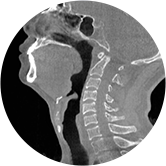

頸椎

FOV 250mm

FOV 350mm